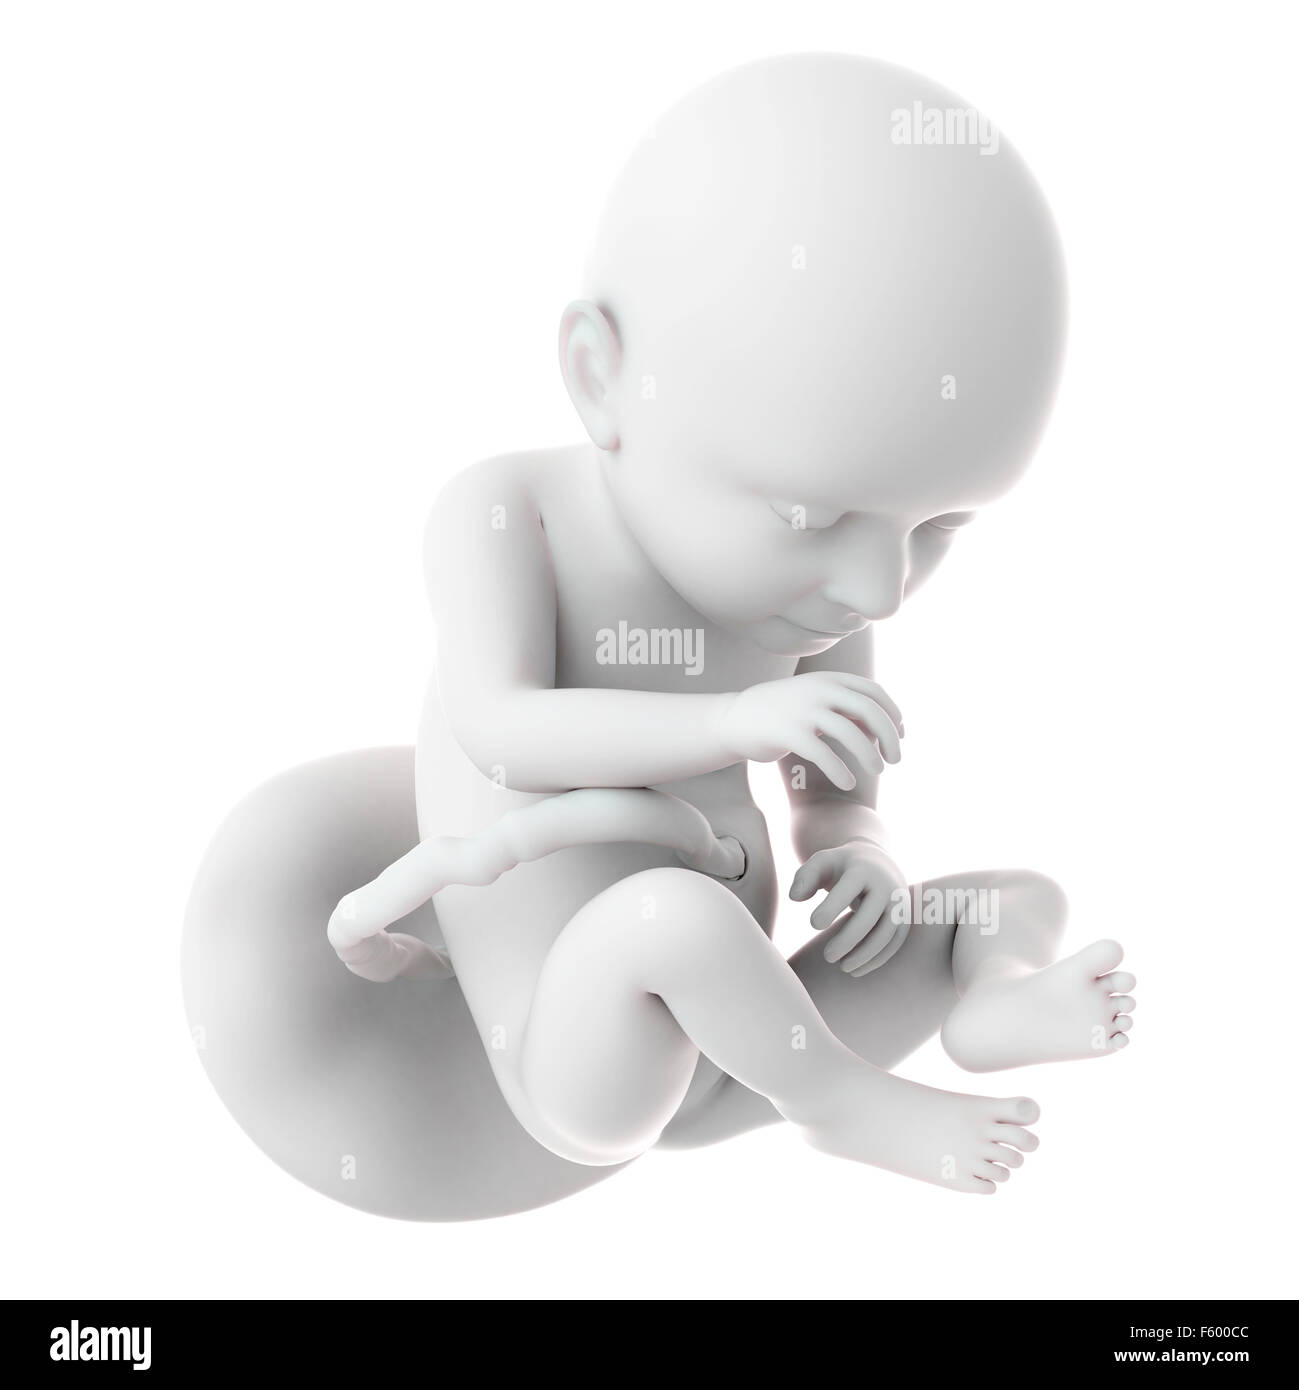

Human Fetus At Week 37 Of Gestation Photograph by Sebastian Kaulitzki …

Human Fetus Age 37 Weeks Photograph by Sebastian Kaulitzki/science …

Human fetus – week 37 stock illustration. Illustration of uterus – 58830075

Weekly development of a human fetus – week 37.

Free 3D fetus 37 development – TurboSquid 1329462